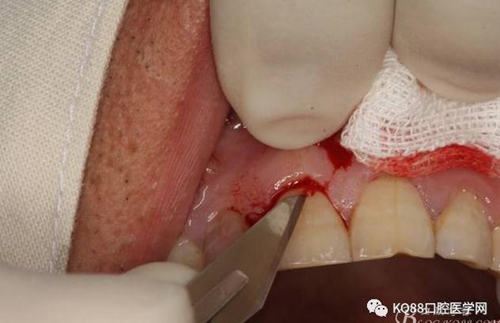

圖6.行唇側(cè)角形切口(11近中垂直切口+齦溝內(nèi)水平切口)垂直切口距離前庭溝約1~2mm。這樣可以減輕術(shù)后腫脹。

圖7. 角形切口中的齦溝內(nèi)切口情況:11號刀片伸進(jìn)齦溝內(nèi)斜切。